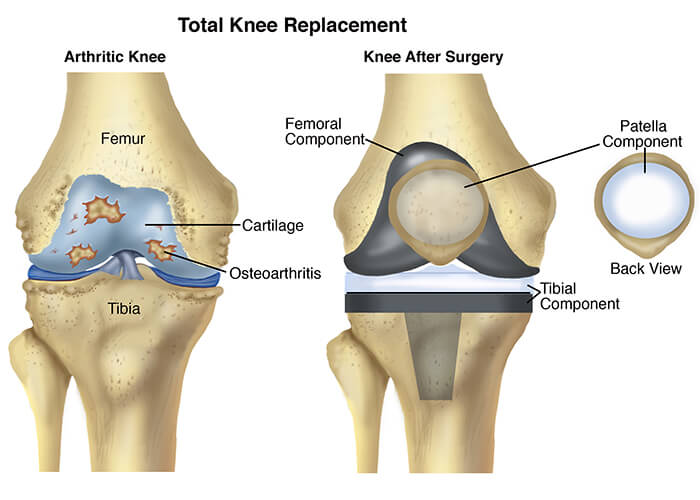

Фотографии и примеры протезирования коленного сустава